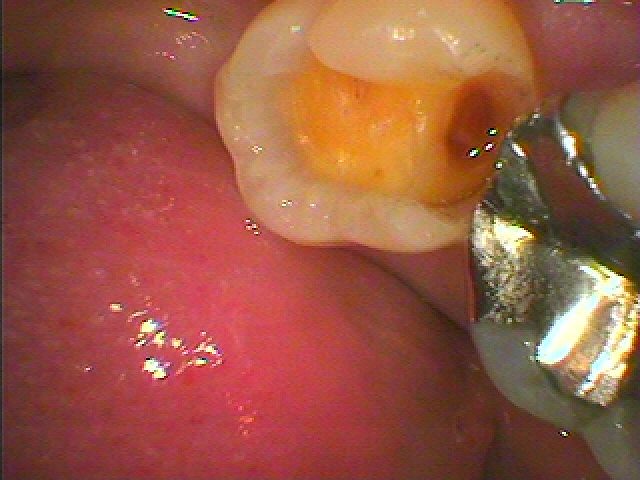

銀歯が外れたので見てほしい 痛みはないが虫歯になっているとのこと|お知らせ |広島市安佐南区の歯科医院 銀歯が外れたので見てほしい 痛みはないが虫歯になっているとのこと トップ お知らせ・ブログ お知らせ 銀歯が外れたので見てほしい 痛みはないが虫歯になっているとのこと 銀歯が外れたので見てほしい 痛みはないが虫歯になっているとのこと 銀歯が外れたので見てほしい 下には黒い虫歯がありました 虫歯を除去していきます CRにて覆罩し型取りを行っていきます セレックセラミックにて修復しています きれいに仕上がりました また銀歯が外れてきました 黒い虫歯があります CRにて覆罩して型取りを行いました 本来の歯のようにきれいに仕上がりました Web診療予約 初めての方へ 選ばれ続ける理由 院内設備について 歯が痛いしみる一般歯科 歯がぐらぐらする歯周病 健康な歯を保ちたい予防歯科 子供の虫歯予防をしたい小児歯科 銀歯をセラミックに審美歯科 白い歯を目指しませんか?ホワイトニング 矯正専門医がいるので安心矯正歯科 抜けた歯を補いたいインプラント・入れ歯 医院案内 スタッフ紹介 メリィハウス歯科クリニックオフィシャルホームページ ラベンダー歯科クリニックオフィシャルホームページ お知らせ・ブログ ホーム 診療科目 一般歯科 歯周病治療 予防治療 小児歯科 審美治療 ホワイトニング 矯正歯科 入れ歯・インプラント マウスピース矯正 初めての方へ 院長・スタッフ 設備紹介 医院案内・アクセス メニューを閉じる